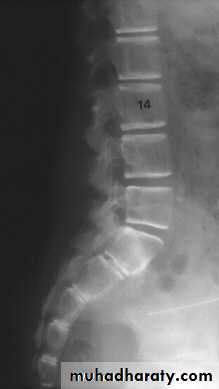

Vertebral bodies show earliest changes:

resorption of horizontal trabeculae

Empty box vertebra: apparent increased density of vertebral endplates due to resorption of spongy bone

Vertebral body compression fractures: wedge, biconcave codfish bodies, true compression